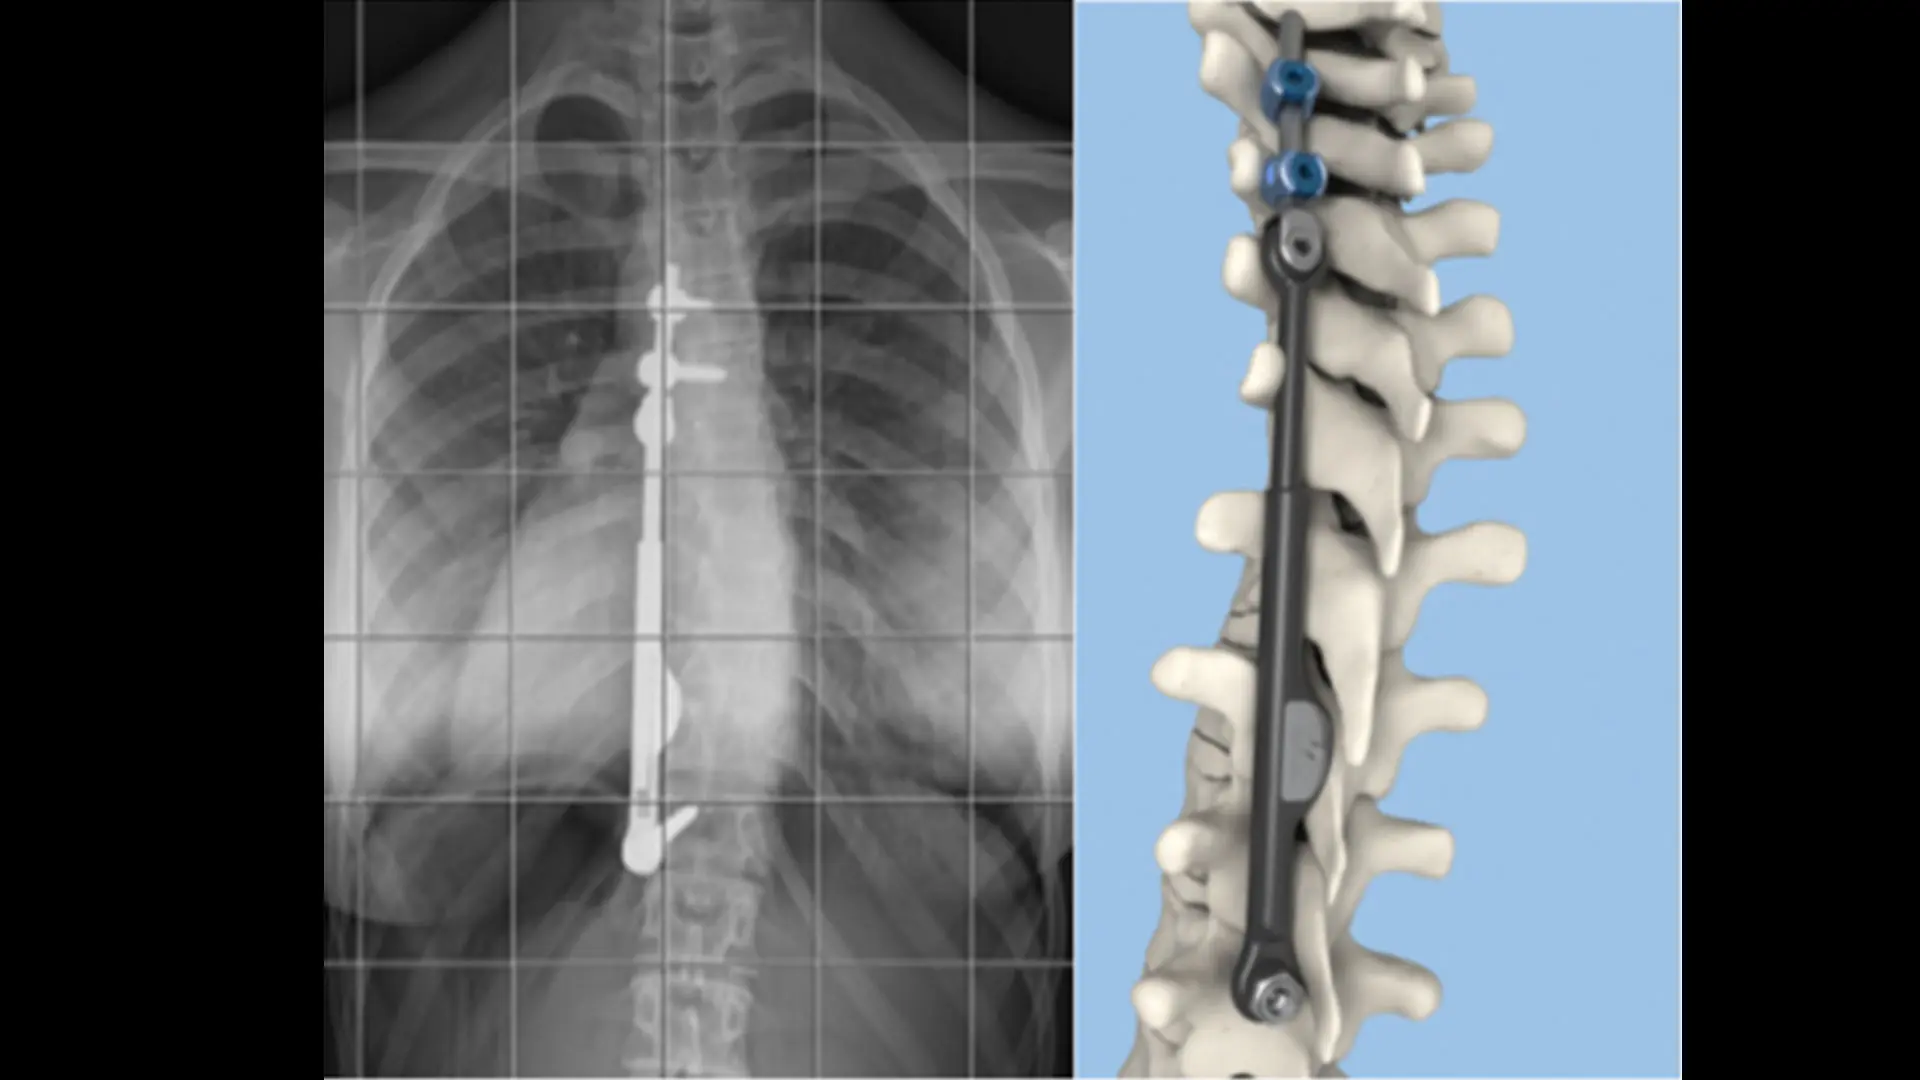

Images of two patients who were treated using the Zimmer Biomet Spine, the Tether™ Vertebral Body Tethering System

During the Tether procedure, the surgeon places an anchor and bone screws made of a titanium alloy into the patient’s spine on the convex (outwardly curved) side of the spinal curve through an anterior approach. With the help of thoracoscopic visualization and very small incisions, a flexible cord made of a polyethylene-terephthalate polymer is secured to the bone screws, and the surgeon applies tension to the cord to partially straighten the spine. After surgery, the cord continues to straighten the spine while the patient grows.